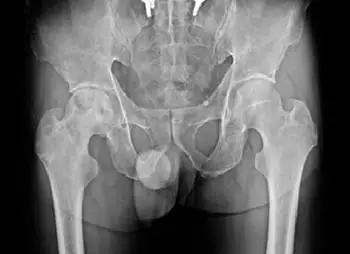

51 歲男性病人主訴右髖關節疼痛數年,髖關節 X光片如附圖,最有可能的診斷為:

本題考查髖關節 X 光片的影像判讀,需鑑別**股骨頭缺血性壞死(avascular necrosis, AVN)**與其他髖關節病變(軟骨下囊腫、骨骼轉移癌、骨髓炎)。51 歲男性,右髖關節疼痛「數年」的慢性病程,合併特定的 X 光表現,是診斷的關鍵。

本題附圖為骨盆腔正面(AP view) X 光片,可見雙側髖關節及骨盆結構。

主要影像所見(右髖關節):

- 右側股骨頭(right femoral head)可見明顯的**硬化(sclerosis)**改變,股骨頭密度不均勻增高

- 股骨頭上外側出現不規則輪廓,提示股骨頭扁平化(flattening)或塌陷(collapse)

- 股骨頭關節面下方可見新月形低密度線(subchondral lucency),符合新月徵(crescent sign),代表關節面下骨折與壞死骨分離

- 股骨頭整體形態失去正常球形輪廓,與對側(左側)正常股骨頭相比有明顯差異

- 無明顯蟲蝕狀(permeative)骨破壞,無骨膜反應(periosteal reaction),不符合惡性腫瘤或急性感染影像

對側比較: 左側股骨頭形態正常,關節間隙保存,骨密度均勻,作為正常參照。

影像結論: 右側股骨頭硬化、扁平化合併新月徵,高度符合**股骨頭缺血性壞死